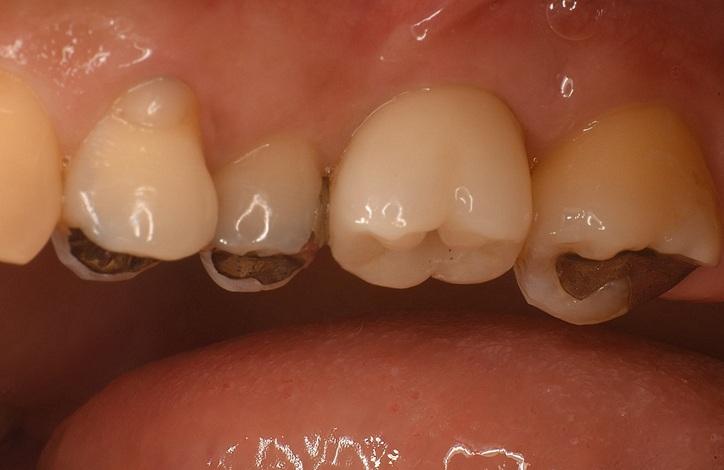

Case5

術前

術後

| 治療名 | サイナスリフトを併用したインプラントブリッジ症例 |

| 治療説明 |

奥歯に入っていたブリッジの支台歯にむし歯が見つかり、やむを得ず抜歯となりました。結果として奥歯が3本分欠損したため、患者さんとの相談のうえ、インプラントによる治療を選択しました。 |

| 治療回数・期間 | 約9ヶ月 |

| 副作用とリスク | ・入れ歯や従来のブリッジと比べ、治療期間が長くなる場合があります。 ・骨造成(GBRやサイナスリフト)を伴う場合、さらに治療期間が延びることがあります。 ・インプラント手術後には、一時的に違和感、痛み、腫れ、出血が生じることがありますが、通常は2日〜1週間で落ち着きます。 ・サイナスリフトは、まれに上顎洞への感染リスクがあるため、術後の経過観察が重要です。 |

| 料金(税込) | 小規模GBR:110,000円 サイナスリフト:220,000円 インプラント一次手術×2本:440,000円 二次手術×2本:110,000円 上部構造〈インプラントブリッジ〉:495,000円 合計:1,375,000円 |